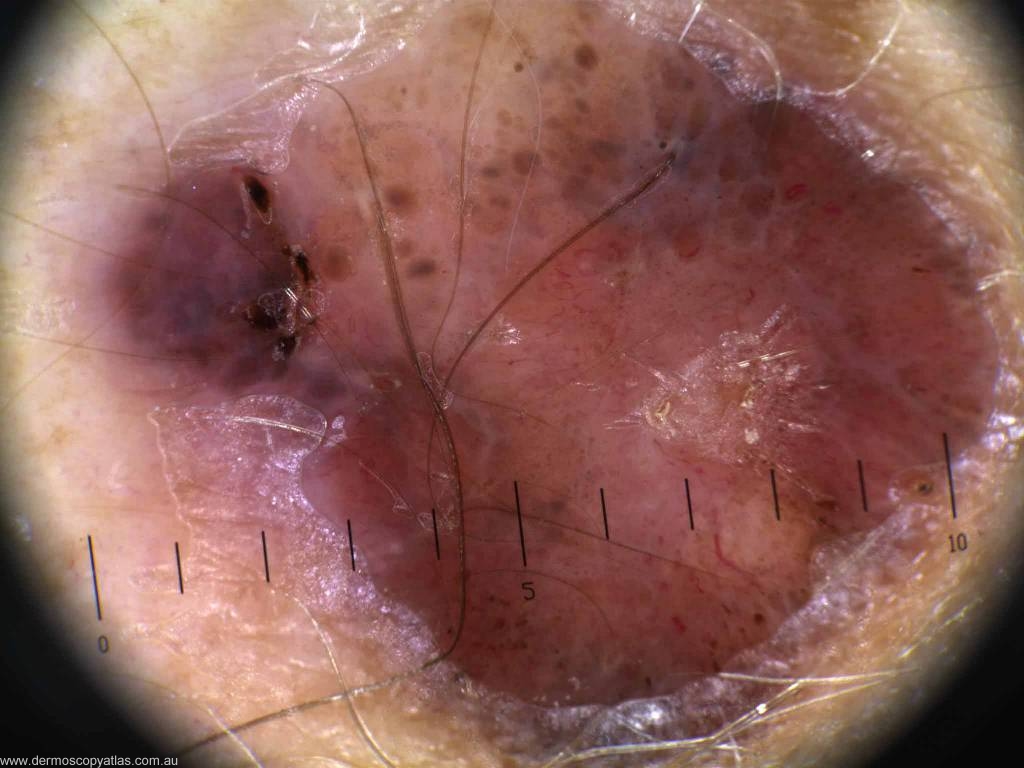

Case 2. 35 year old female (type II skin ) Lesion has been present for some time, thinks it may have changed in the last 12 months, and has been bleeding intermittently for about 2 months. R forearm.

Question: What is your diagnosis now? Consider Merkel Cell tumour, Dermatofibrosarcoma protuberans, BCC, Melanoma, Compound nevus, Atypical fibrosarcoma.